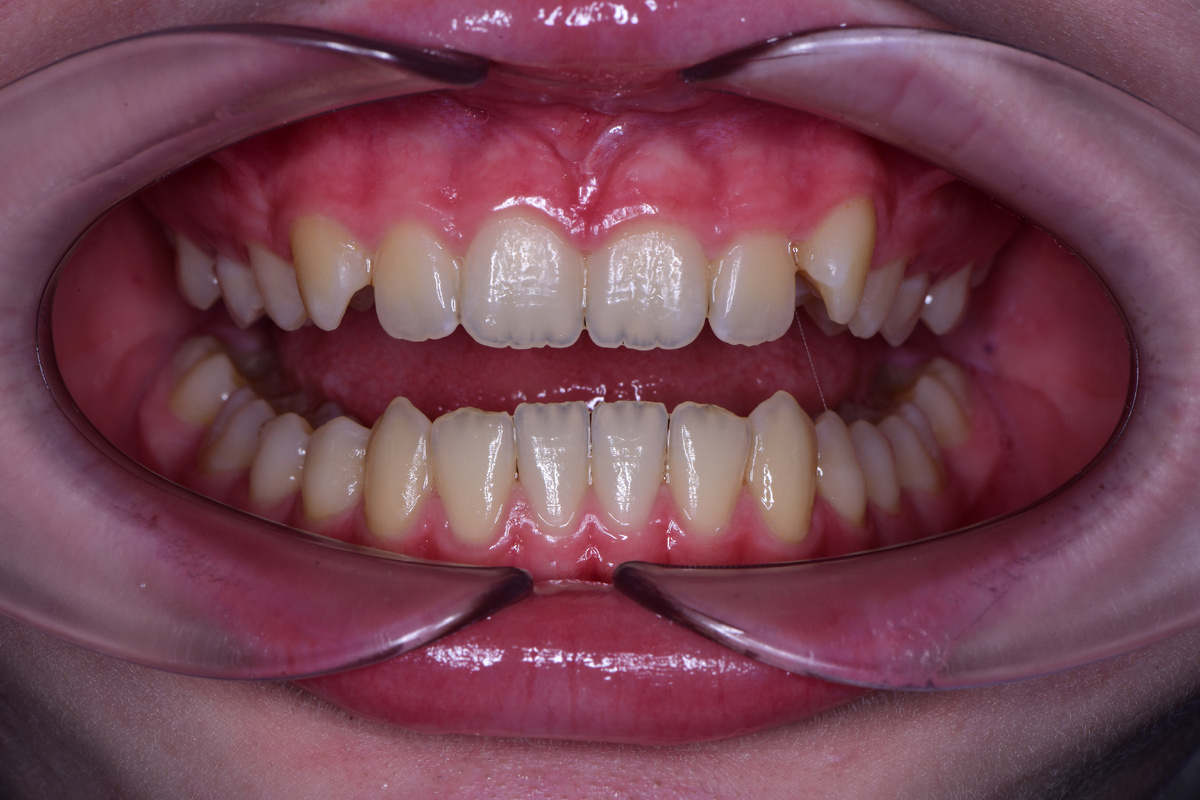

Первым делом мы провели диагностику, осмотрели зубы и десны пациентки. Десны выглядели воспаленными, покраснение и отек особенно заметны в области центральных резцов и клыков.

Машины десны выглядят массивными и воспаленными

Причина — налет. Его много, и он лежит плотным слоем, особенно на клыках. Зубы выглядят матовыми, шероховатыми, без естественного блеска. Очевидно, что Маша недостаточно тщательно их чистит.

Увидели заметный результат: зубы очистились от желтого налета и других загрязнений, поверхность стала гладкой.

Результат порадовал и нас, и Машу